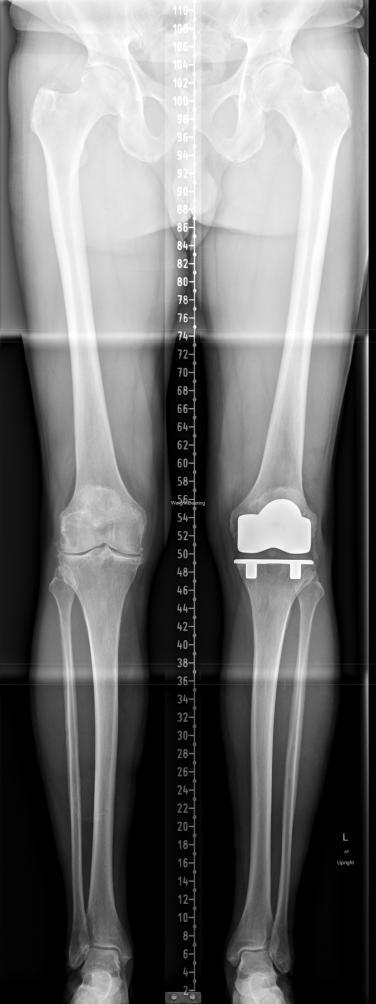

During 2014 I was experiencing a lot of pain in my knees, in particular, in my left knee. On September 10th 2014 weight bearing X-rays taken of my knees (see image in the link below) revealed no gap between femur and tibia on left knee (there s/b a gap), and, notice whitening of bones where they wee touching (because they had been beating on each other for a while). The doctor said I needed a total knee joint replacement on my left knee, and, my right knee was also bad and I would know how soon I wanted it replaced after getting the left knee replaced, I said not yet - I had found Aleve pain medication, he said call him when Aleve didn't work anymore. Aleve was helped with the pain in my left knee for a while before becoming unable to walk and on March 17, 2015 the total right knee joint was replaced at Sutter Davis Hospital.

Weight bearing X-ray, 10SEP14, 04MAY15, 23MAY19 (click on X-ray to enlarge):

X-ray by Sutter Davis Hospital